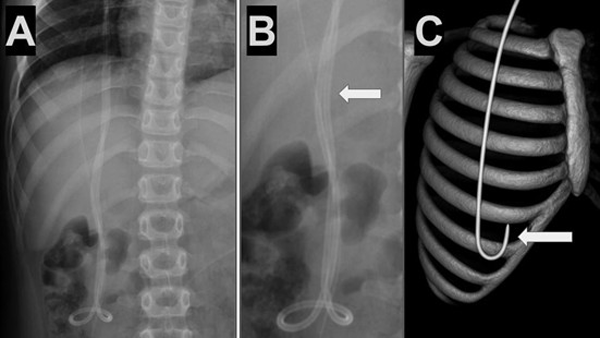

Caso 1. Paciente masculino de 6 años con antecedentes de hidrocefalia secundaria a hemorragia intraventricular del prematuro y colocación de DVP a los 9 meses de vida que presentó cuadro clínico de 12 horas de evolución caracterizado por cefalea, vómitos y somnolencia. Tomografía de cerebro evidenció dilatación del sistema ventricular respecto a estudios previos. Radiografías de recorrido del sistema mostraron la migración retrógrada del catéter distal (Figura 1).

Figura 1. Caso 1: A) Se observa en Rx de tórax y abdomen (frente) catéter distal a nivel abdominal con migración retrógrada. B) Magnificación de Rx de abdomen que evidencia catéter en doble caño con signo radiológico del “caño de escopeta” o “signo del anzuelo” (flecha blanca).